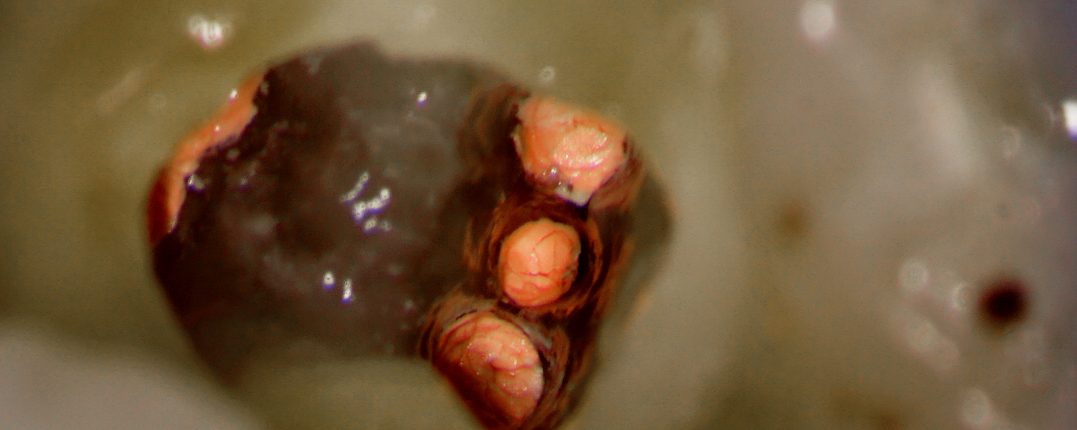

#30 RCT – 3 Distal anatomy – Truss access

#30 deep distal margin. Done in 2 visits. Gingivectomy and Pre-endo done. All canals shaped to 4% 25 obturated using WVC.